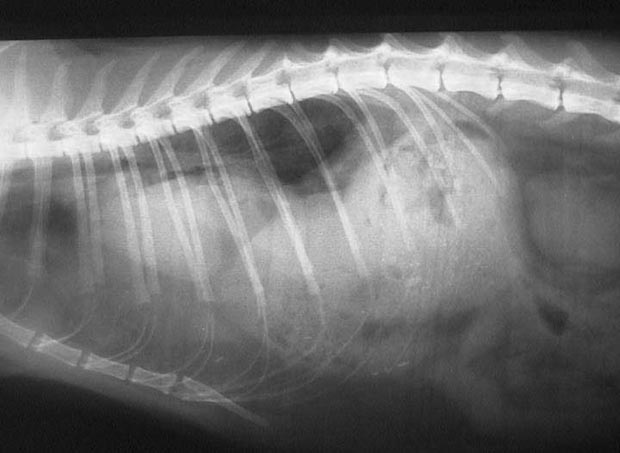

This cat has a diaphragmatic hernia. Notice how you cannot readily see the diaphragm, and how the heart is elevated and the lungs compressed due to the liver being in the chest.